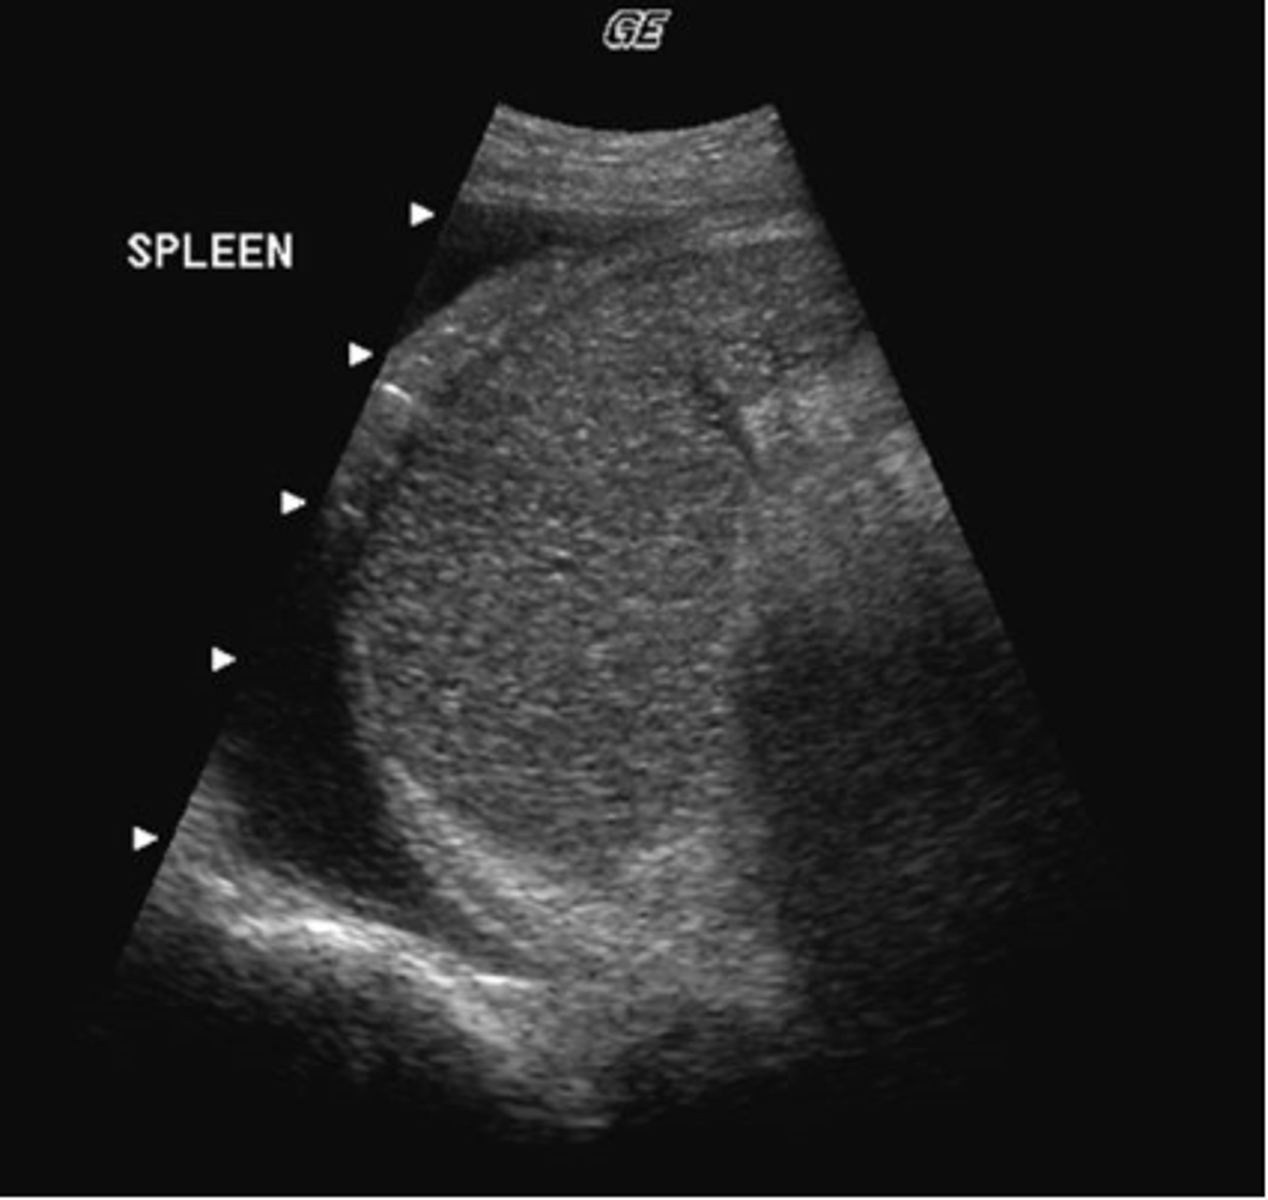

b. splenic and retroperitoneal varices

A 49-year-old male presented with a clinical history of liver cirrhosis and portal hypertension. In the transverse image below, multiple hypoechoic structures are seen at the splenic hilum and between the kidney and spleen. What is the most likely etiology of these structures.

a. multiple aneurysms of the splenic artery

c. loculated ascites

d. polycystic kidney disease

e. fluid-filled loops of bowel